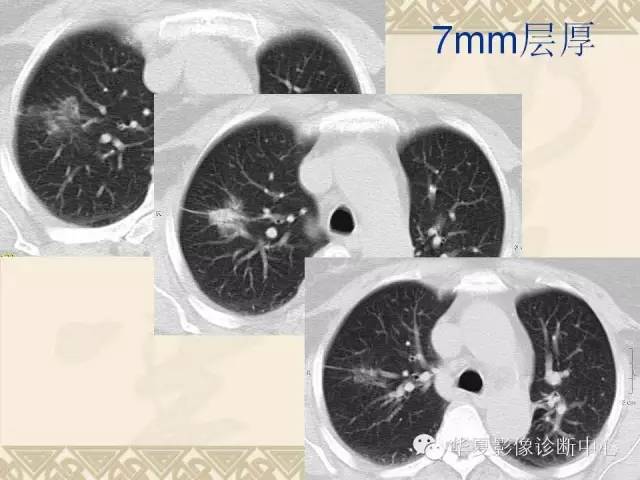

肺内磨玻璃样结节的影像诊断与处理对策